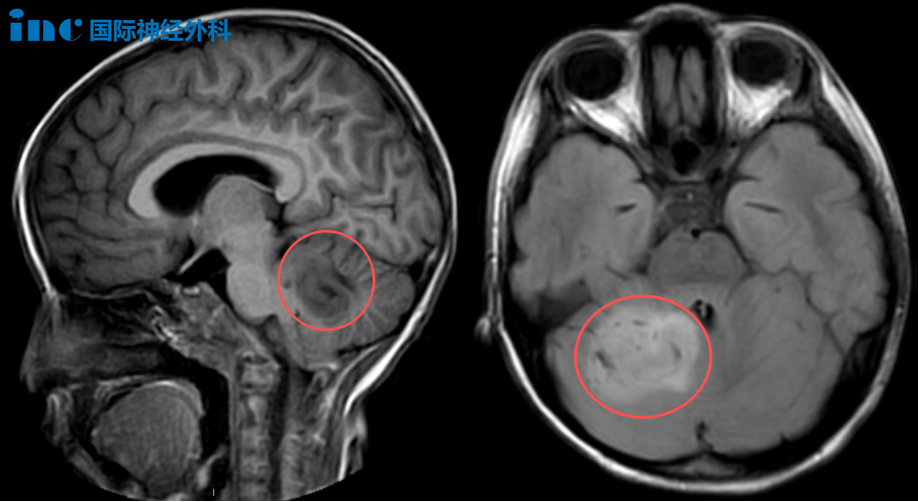

到了9月份,由于乐乐持续性的头晕、呕吐和疲累,竟查出了一个位于小脑的占位,怀疑为胶质瘤。这个肿瘤令乐乐止不住地发晕,尤其是在站立和行走的时候,导致孩子日常总是恹恹的,看得父母心疼不已。

询问了很多医生,却被告知“孩子的肿瘤可能与脑干粘连,手术难度大。”无法如此轻易地放弃女儿,乐乐父母决定再咨询一下巴教授。没想到,巴教授的看法截然不同:“该病变并未累及脑干本身。对他们而言,切除难度较大,但对我来说并非难事,我能做到。”